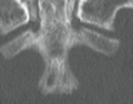

Lester E. Mertz, MD; Luciana Funtowicz, MD; Elizabeth B. Windgassen, MD

<p><strong><img alt="birefringent crystals" height="90" src="/sites/default/files/images/Screen%20shot%202012-10-12%20at%2010.51.40%20AM.png"...